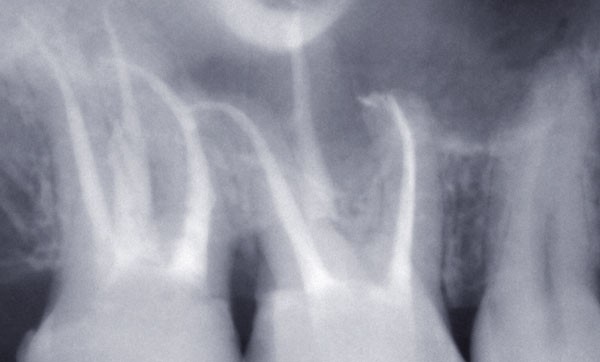

Caries profondes dans les secteurs postérieurs : remontée de marge vs élongation coronaire

La question posée concerne les restaurations proximales des secteurs postérieurs. Ces situations cliniques sont complexes à plusieurs titres : l’accès peut être compliqué, étanchéifier la zone avant collage n’est pas toujours évident et l’accès au brossage n’est pas aisé. Le contrôle de l’adaptation des bords et la qualité du profil d’émergence sont essentiels puisque participant au développement des caries initiales, aux reprises de carie mais aussi au développement et à l’aggravation des maladies parodontales, soit par la présence du matériau lui-même, soit par la gêne qu’il provoque quant à l’accès à l’hygiène orale [1,2].